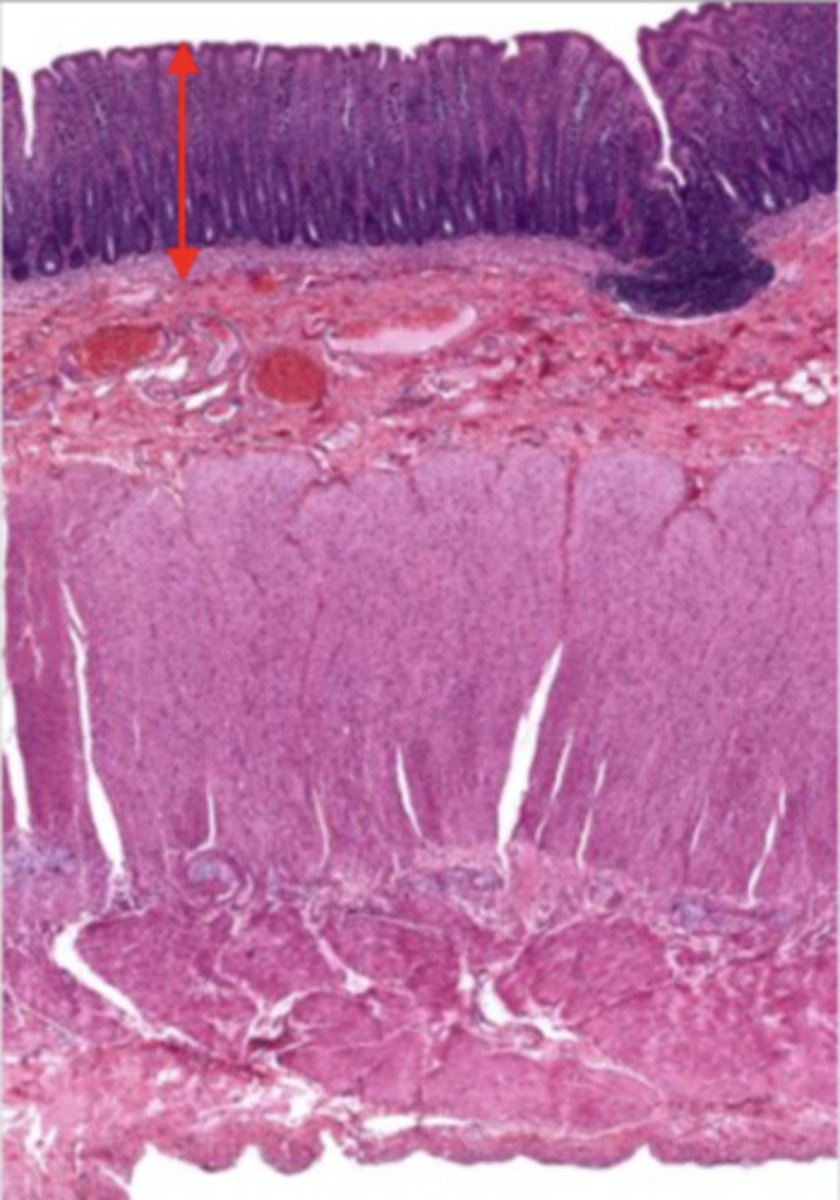

cardiac stomach (histology)

simple columnar epithelium

what kind of epithelium lines the mucosa of the cardiac stomach?

gastric pit (cardiac stomach)

lumen (cardiac stomach)

mucosa (cardiac stomach)

mucosal epithelium (cardiac stomach)

lamina propria (cardiac stomach)

muscularis mucosa (cardiac stomach)

submucosa (cardiac stomach)

contains glands and blood supply

muscularis externa (cardiac stomach)

serosa/adventitia (cardiac stomach)